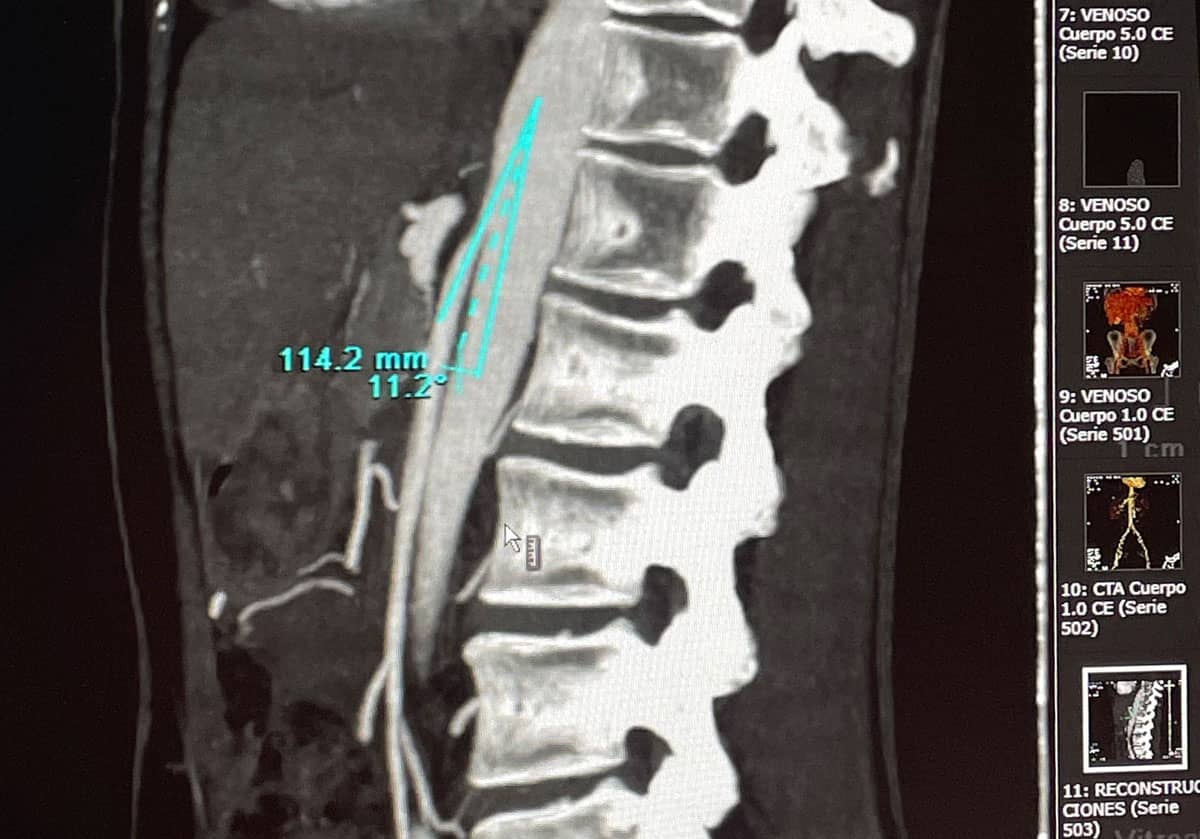

Como siempre es fundamental hablar con el paciente para que nos cuente sus síntomas. Realizamos también una exploración física para ver si existen varices en piernas o varices vulvares. Además, un examen ginecológico por parte del especialista también es fundamental para valorar otras causas de las molestias del paciente. A continuación, nuestra prueba de imagen inicial y fundamental es el eco-doppler abdominal o transvaginal y de miembros inferiores. Una vez confirmado o con una alta sospecha se puede completar el diagnóstico con un angioTc o una Resonancia Magnética para descartar otras causas y valorar la anatomía.

En último lugar, el diagnóstico de confirmación nos lo da la flebografía que generalmente se realiza en el mismo acto en que se tratan.